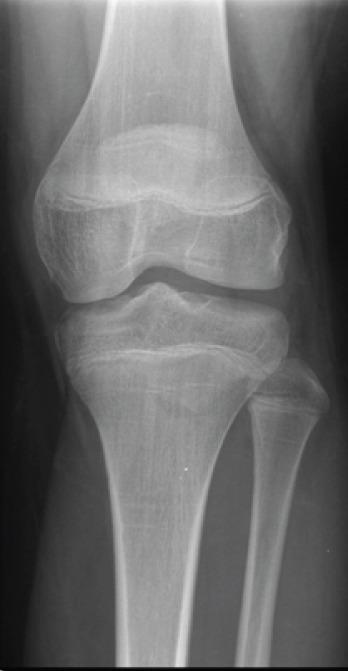

A 6-year-old boy with went to the emergency department after suffering trauma in his left knee. In the performed X-ray, no osteoarticular injury was identified. Conservative treatment with immobilization with cast was performed. After removing the immobilization, the initial evolution was positive with no pain on mobilization. A few months later, he went again to the emergency department due to new left knee trauma. On examination, he had pain in the mobilization of the left knee, especially in knee extension which was not entire. Image study led to the diagnostic of avulsion fracture of the anterior tibial spines. The fracture was classified as modified Meyers and Mckeever Type II and conservative treatment with cast immobilization was performed. In the clinical and imaging revaluation done 4 weeks later, an evolution to non-union of the anterior tibial spine was noticed. At arthroscopy, non-union of tibial spines was confirmed, with elephant paw bone fragment with loss of its right to domicile. Open surgery was performed with debridement, cruentation, and fixation of the bone fragment to the tibia with a screw. The patient had favorable post-operative evolution with fracture consolidation, preserved mobility, no instability of the joint, and no limitation in daily and school activities. Four years after the initial surgery, a second procedure was performed for the removal of the screw. During 7 years of follow-up, no limitations or sequels were found.

一名6岁男孩左膝受伤后前往急诊科。在进行的X线检查中,未发现骨关节损伤。采用石膏固定进行保守治疗。去除固定后,最初的恢复情况良好,活动时无疼痛。几个月后,他因左膝再次受伤再次前往急诊科。检查时,他左膝活动时疼痛,尤其是在不完全伸直时。影像学检查诊断为胫骨前棘撕脱骨折。该骨折被分类为改良迈尔斯和麦基弗II型,并再次采用石膏固定进行保守治疗。在4周后进行的临床和影像学复查中,发现胫骨前棘出现骨不连。关节镜检查证实胫骨棘骨不连,有象爪状骨块且失去原位。进行了开放手术,包括清创、植骨,并使用螺钉将骨块固定于胫骨。患者术后恢复良好,骨折愈合,活动度保留,关节无不稳定,日常和学校活动无受限。初次手术后四年,进行了第二次手术取出螺钉。在7年的随访中,未发现任何限制或后遗症。